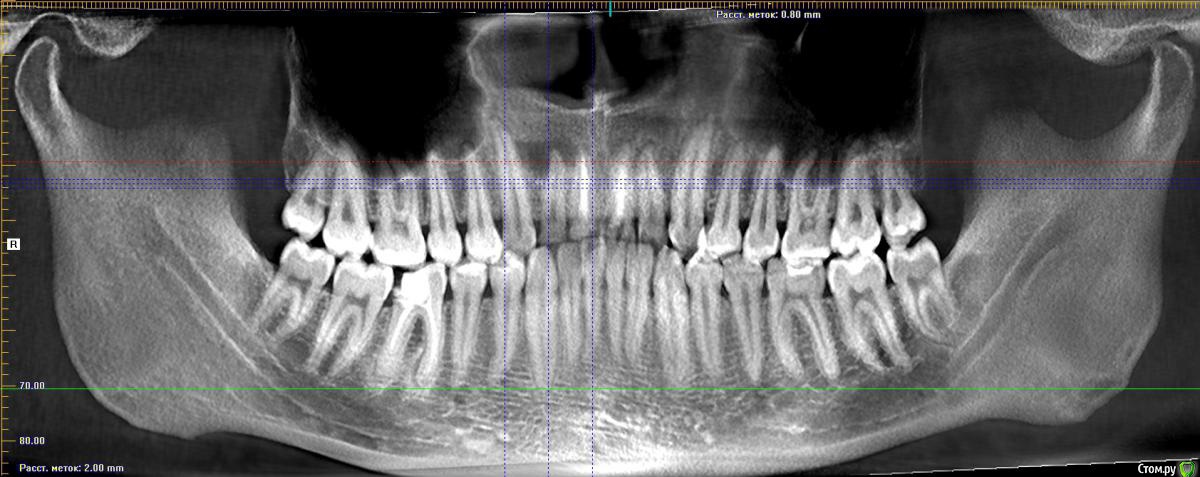

Shelly2000 Опубликовано 22 апреля, 2017 Поделиться Опубликовано 22 апреля, 2017 Здравствуйте! Сыну 22 года, но с лечением зубов уже сталкивался неоднократно. Пару недель назад отвалилась существенная часть коронки второго правого резца. Сделали КТ, посетили несколько клиник. Мнения разных стоматологов совпали только в одном - есть киста, и её можно попробовать лечить. Дальше пошли сильные расхождения в методике, сроках и вероятности достижения положительного результата. Где-то считают, что лечебный препарат (каласепт) нужно закладывать в этот зуб дважды, с промежутком в 10-14 дней, а после этого пломбировать канал. Где-то называют сроки в 1-2 месяца и уверяют, что для правильного лечения необходимо вскрывать соседний запломбированный 11-й зуб и закладывать лекарство и через него тоже (при этом именно плохое пломбирование 11-го зуба считают самой вероятной причиной образования кисты). Самая длительная версия - полгода-год, с регулярной ежемесячной сменой лекарства в больном зубе, причём сразу предупредили, что после первой закладки десна может опухнуть, так как этим перекроется путь выхода нагноений, которые сейчас через зуб малыми количествами незаметно выходят. В случае, если такое лечение не даст положительного результата, была описана хирургическая процедура механического удаления кисты через разрез с нёбной стороны.При всех описанных манипуляциях нигде не давали гарантию, что зуб удастся спасти, а в одной клинике даже сразу просчитали стоимость установки имплантата, но опять же - только после того, как ситуация с костной тканью нормализуется.Хотелось бы понять, сколько реально может занять лечение, так как до его завершения невозможно заниматься протезированием коронки на этот и соседний зуб. Какой из вариантов лечения правильный?Сделал скрины из КТ. Если не смутит объём полного исследования - вот ссылки на версию в iCATVision: https://yadi.sk/d/-kkaw4FG3HEGA3и версию в Planmeca: https://yadi.sk/d/eXHITZmn3HEGCt Спасибо за потраченное время! Ссылка на комментарий